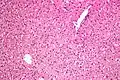

Micrograph showing ground glass hepatocytes. H&E stain.

In liver pathology, a ground glass hepatocyte, abbreviated GGH, is a liver parenchymal cell with a flat hazy and uniformly dull appearing cytoplasm on light microscopy. The cytoplasm's granular homogeneous eosinophilic staining is caused by the presence of HBsAg.

The appearance is classically associated with abundant hepatitis B antigen in the endoplasmic reticulum, but may also be drug-induced.[1][2] In the context of hepatitis B, GGHs are only seen in chronic infections, i.e. they are not seen in acute hepatitis B.

Several different types of GGHs are recognized:[4]

- Type I - morphologically consist of GGHs that are scattered singly and have weak Pre-S2 positive immunostaining.

- Type II - morphologically consist of GGHs that are in clusters and have Pre-S2 negative immunostaining.

There is some evidence to suggest that type II GGHs predispose to hepatocellular carcinoma.[2][5]